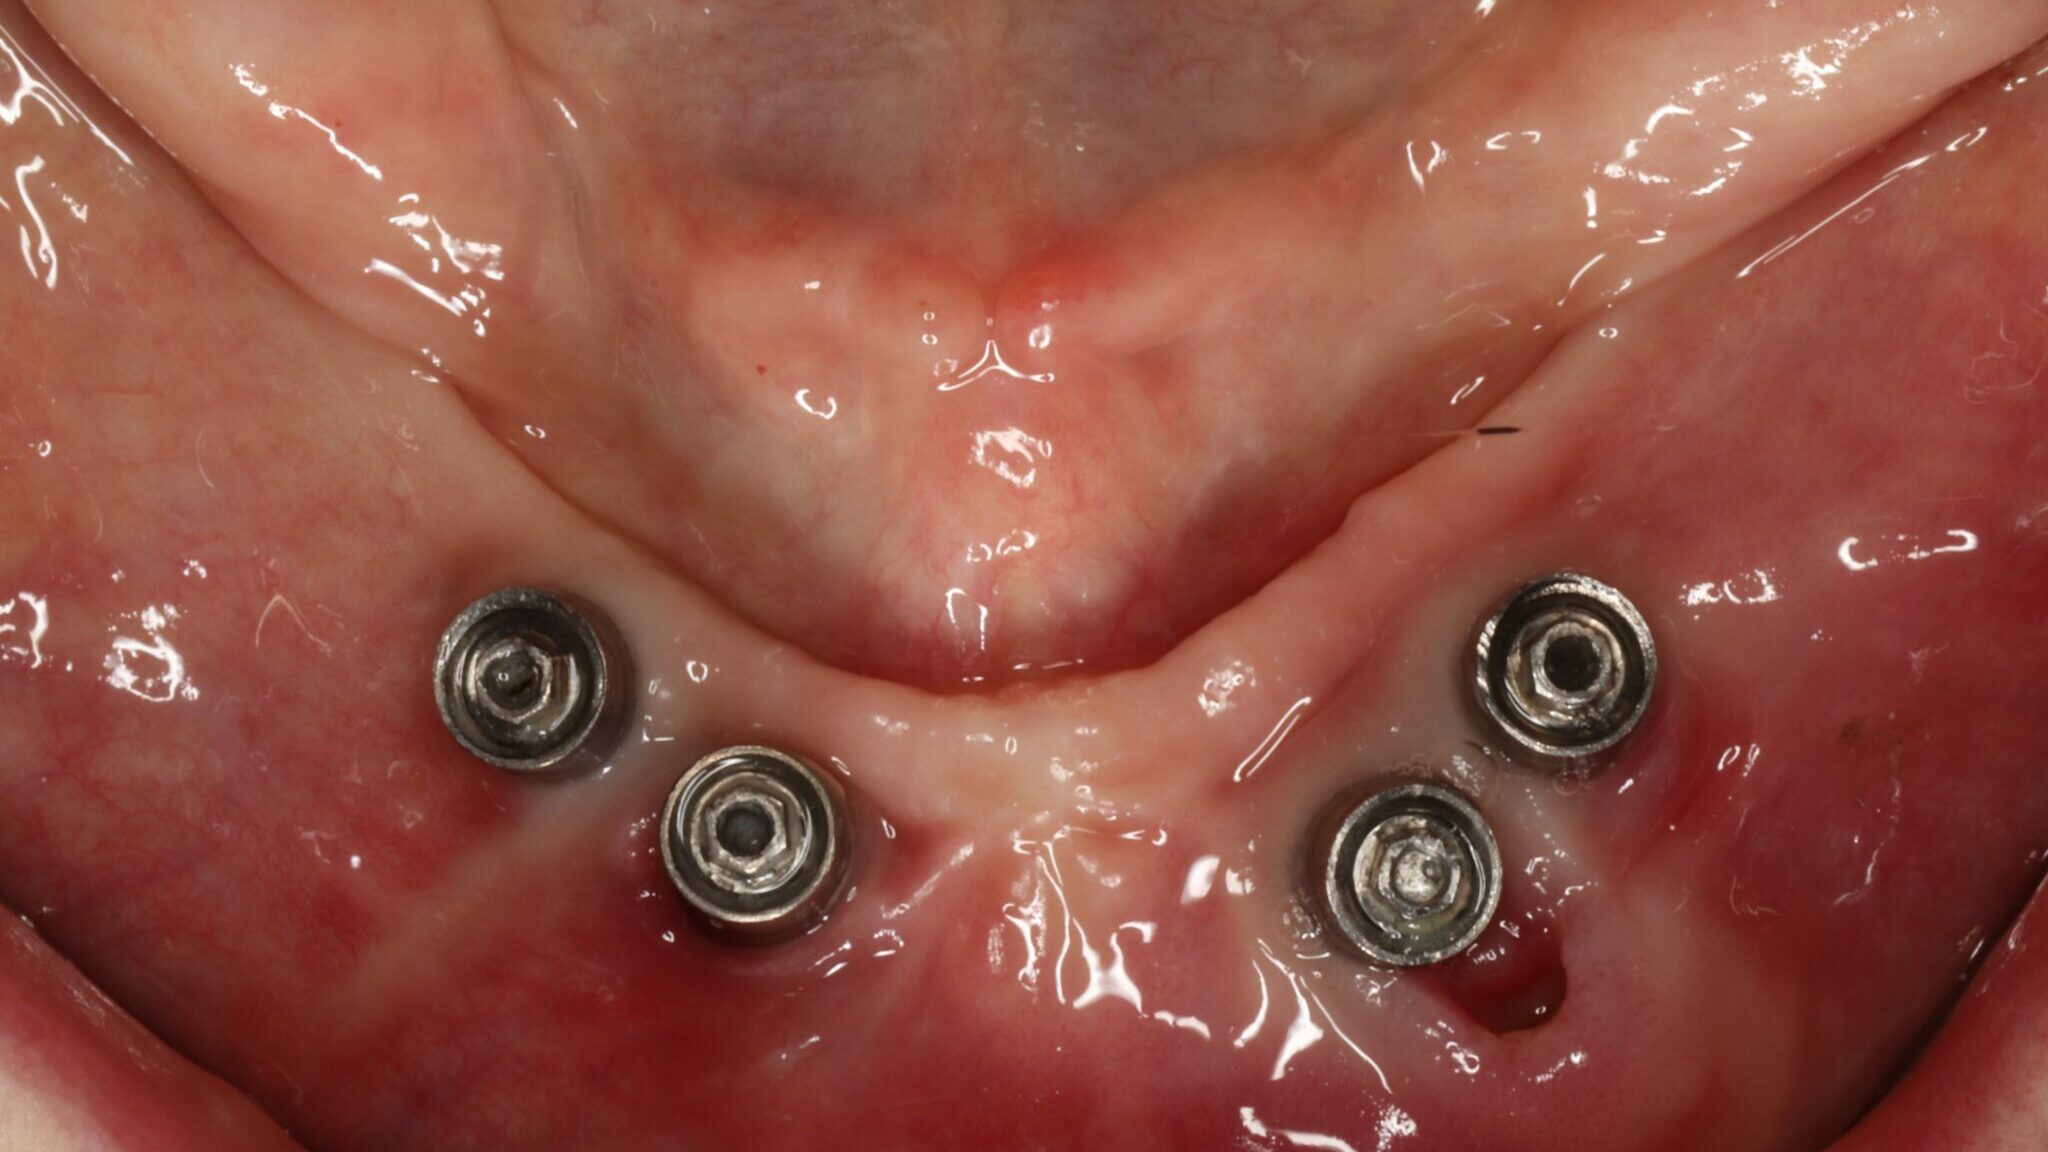

Alternative Verification Jig for the Assessment of Mandibular Flexure

Wong-fig-5-thumbnail alternate text for this image

PATIENT: M, Age: 62, ASA II (pharmacological management of hypertension and high cholesterol). CHIEF COMPLAINT: Patient presented for the fabrication of a mandibular implant supported fixed prosthesis, with implants having been placed 6 months ago. CLINICAL FINDINGS: Maxillary arch had a fixed implant supported prosthesis with implants in the 17, 16, 14, 13, 22, 23, … Read more